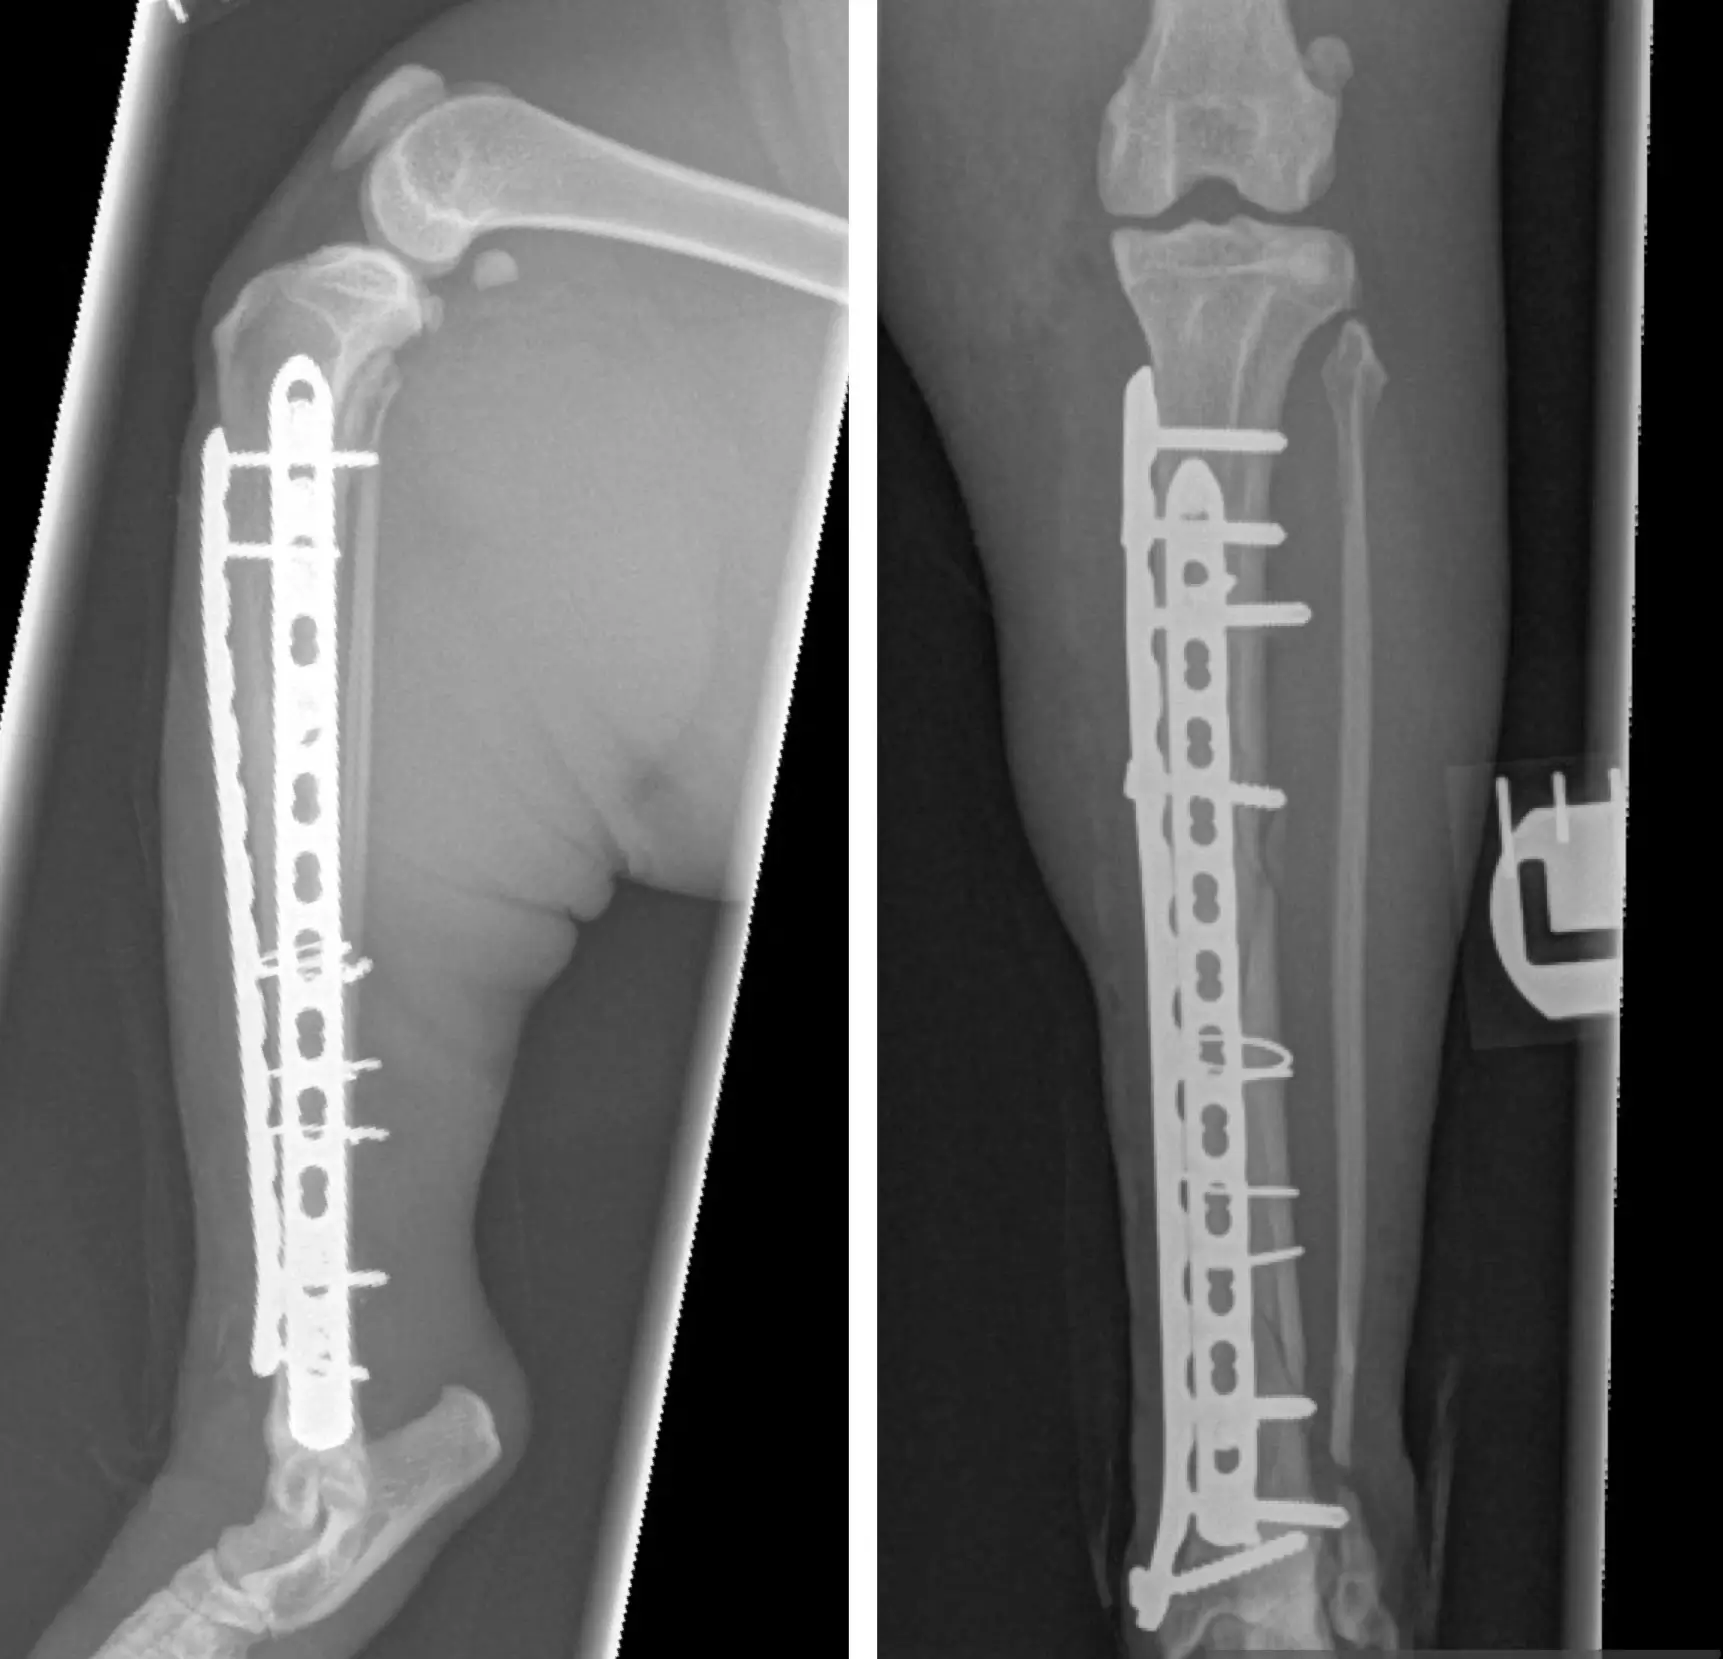

X-Ray

• Fractures

• Trauma

• Digital radiography (X-rays) for fast and accurate assessment of musculoskeletal, pulmonary, gastrointestinal, and urogenital disorders.